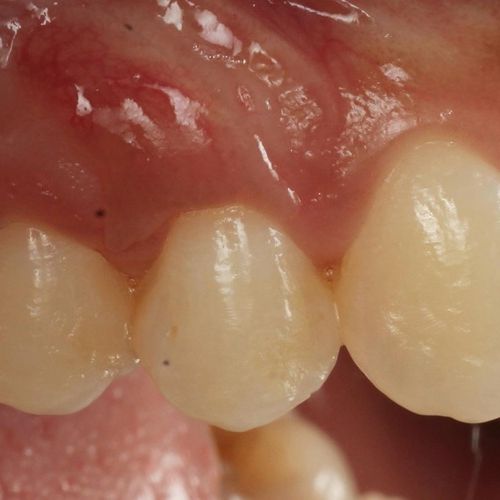

![]() | ![]() |

| Free gingival graft surgery’ to thicken gum and prevent further recession | Gum recession surgery in an aesthetic site |